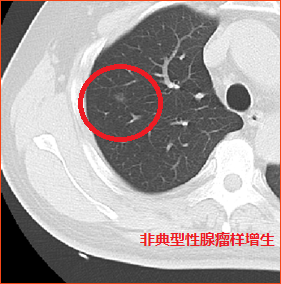

肺结节按性质分为良性结节和恶性结节。常见的良性结节有炎症、结核瘤、错构瘤、肺内淋巴结、血管瘤等。恶性结节有原发性肺癌和转移瘤等。还有一些是癌前病变,比如非典型性腺瘤样增生,这些癌前病变随着病变的进展,可发展为肺癌。据统计,结节越大恶性概率越大。

典型的错构瘤(内有爆米花样钙化)